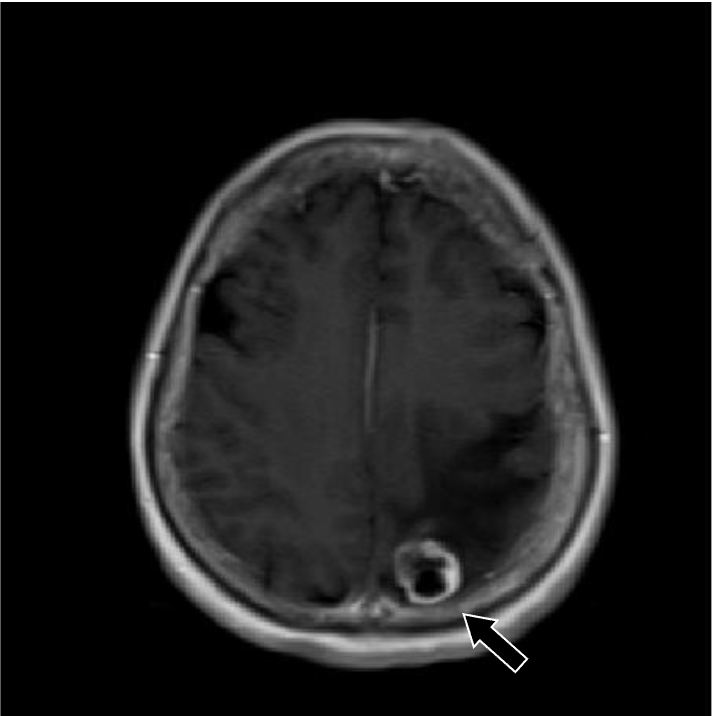

202X年より右手指知覚障害、頭痛を自覚。数日後から頻回嘔吐や右下肢運動障害があり、頭部造影MRIにて精査。既往に転移性肺腫瘤の治療歴あり。

症例解説

201X年腎細胞癌に対して手術を施行。術後経過で肺転移が出現。外科的切除および化学療法にて縮小を維持していた。202X年神経症状が出現し、頭部造影MRIにて左頭頂葉の孤発性脳転移と診断された。開頭腫瘍摘出術および定位照射を行い、再発なく経過している。

造影MRI検査は単純MRI検査と比較して、追加病変の検出能や診断精度の向上が示されている。造影MRI検査は、非腫瘍性白質疾患(慢性微小血管虚血性疾患など)を転移性腫瘍と鑑別する上でも有用である。脳腫瘍では腫瘍周囲に血管原性浮腫を認める場合があるが、高悪性度の原発性脳腫瘍と比較して、転移性脳腫瘍では腫瘍径に対する血管原性浮腫の面積が広いことが報告されている。単純MRI検査では腫瘍径を過大評価する可能性があり、術前・放射線治療計画等に際して造影MRI検査による適切な評価が求められる。